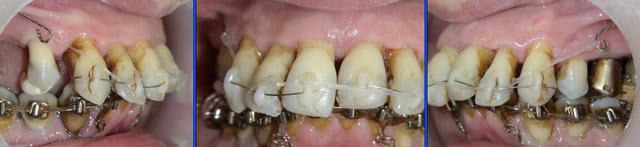

Voici le cas à 3 semaines. Les diastèmes sont complètement fermés.

J’ai rajouté une traction au niveau des incisives centrales. Il y a donc pour le même groupe de dents deux tractions, une au niveau des canines et une autre au niveau des centrales.

Voyez la qualité de la cicatrisation au niveau de l’émergence de la ligature de la muqueuse inférieure.

A trois mois (photos f0), remplacement du fil élastique par un fil NiTi enfilé dans les lumières de composite. Un chaînette élastomérique continue la traction.

A six mois (photos f1, f2 et f3), résultats à ce stade et panoramique de contrôle.